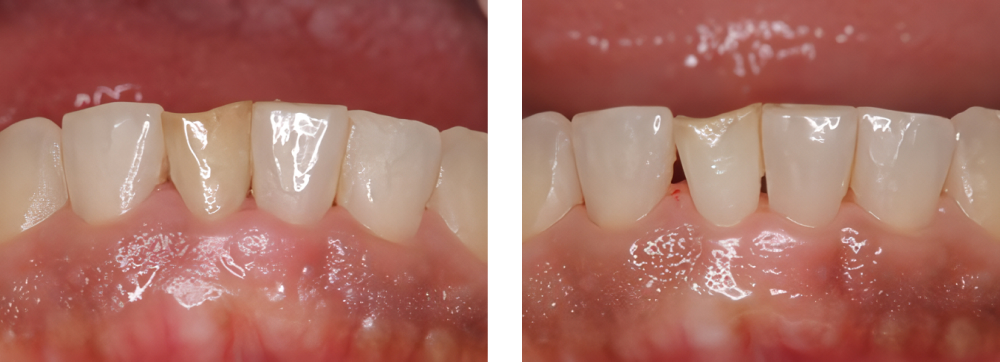

審美歯科

| 治療内容 | ウォーキングブリーチ後ジルコニアセラミックにて治療を行った |

|---|---|

| 治療期間・回数 | 4カ月・10回 |

| 費用 ※自由診療となります |

ウォーキングブリーチ:11,000円 プロビジョナルレストレーション:2,200円 ファイバーコア:16,500円 ジルコニアセラミック:132,000円 |